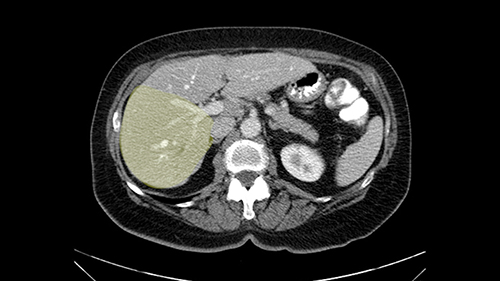

So when doing a major liver resection, obviously we would focus on a few issues. The first is hepatic parenchyma: is there adequate liver, residual liver and orientation and ratio of the right to left lobe here is pretty normal. It looks like its about 60:40 or 70:30, and because its only a right lobe, I probably wouldn’t do any volumes assuming she has normal liver function which I think she does. The only additional feature of interest is that she has received chemotherapy and one can see the effect of chemotherapy on the density of the liver but again, it doesn’t usually cause significant problems with a short course of neoadjuvant chemotherapy, or liver failure.

I am Professor Jacques Belghiti, hepatobiliary surgeon. I practiced at Beaujon Hospital at Paris Diderot University Paris 7. I will discuss the case of a 65-year old patient who has hepatic metastases from a colon cancer operated on one year before. Two particular points with this patient: She has had a cholecystectomy at the time of colectomy, and at the discovery of the lesions in which there were 3, all located in the right liver, we noted the existence of biliary dilatation. This biliary tract dilatation could have been a consequence of the cholecystectomy, or due to a particular form of metastasis with biliary infiltration; and my impression is that the second hypothesis should be supported for two reasons. The first reason is that on the initial CT scan, we had a feeling that the biliary tract dilatation was associated with a small tumor/lesion. The second reason is that the dilatation decreased after several courses of chemotherapy. I don’t know how many courses of chemotherapy she had, but in any case, there exists some lesions of the hepatic parenchyma, with steatosis that may have been a consequence of this chemotherapy. After several courses of chemotherapy, we see at least 2 lesions persisting in the posterior sector of the right liver and dilatation of the biliary tracts. There might be another lesion at the junction of Sg 5 and 8. So this patient should now be operated on since we are faced with lesions that persisted after chemotherapy.